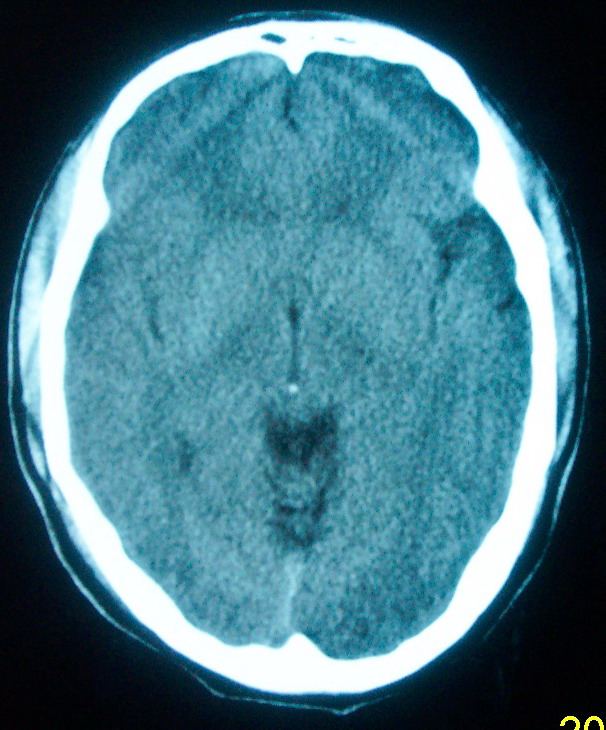

m     29    外伤1天   ct发现左额脑沟异常   请分析

我认为仅仅是左侧额叶脑回局部发育不良,脑沟与蛛网膜下腔略扩大而已没有巨脑回、硬膜下积液等情况。